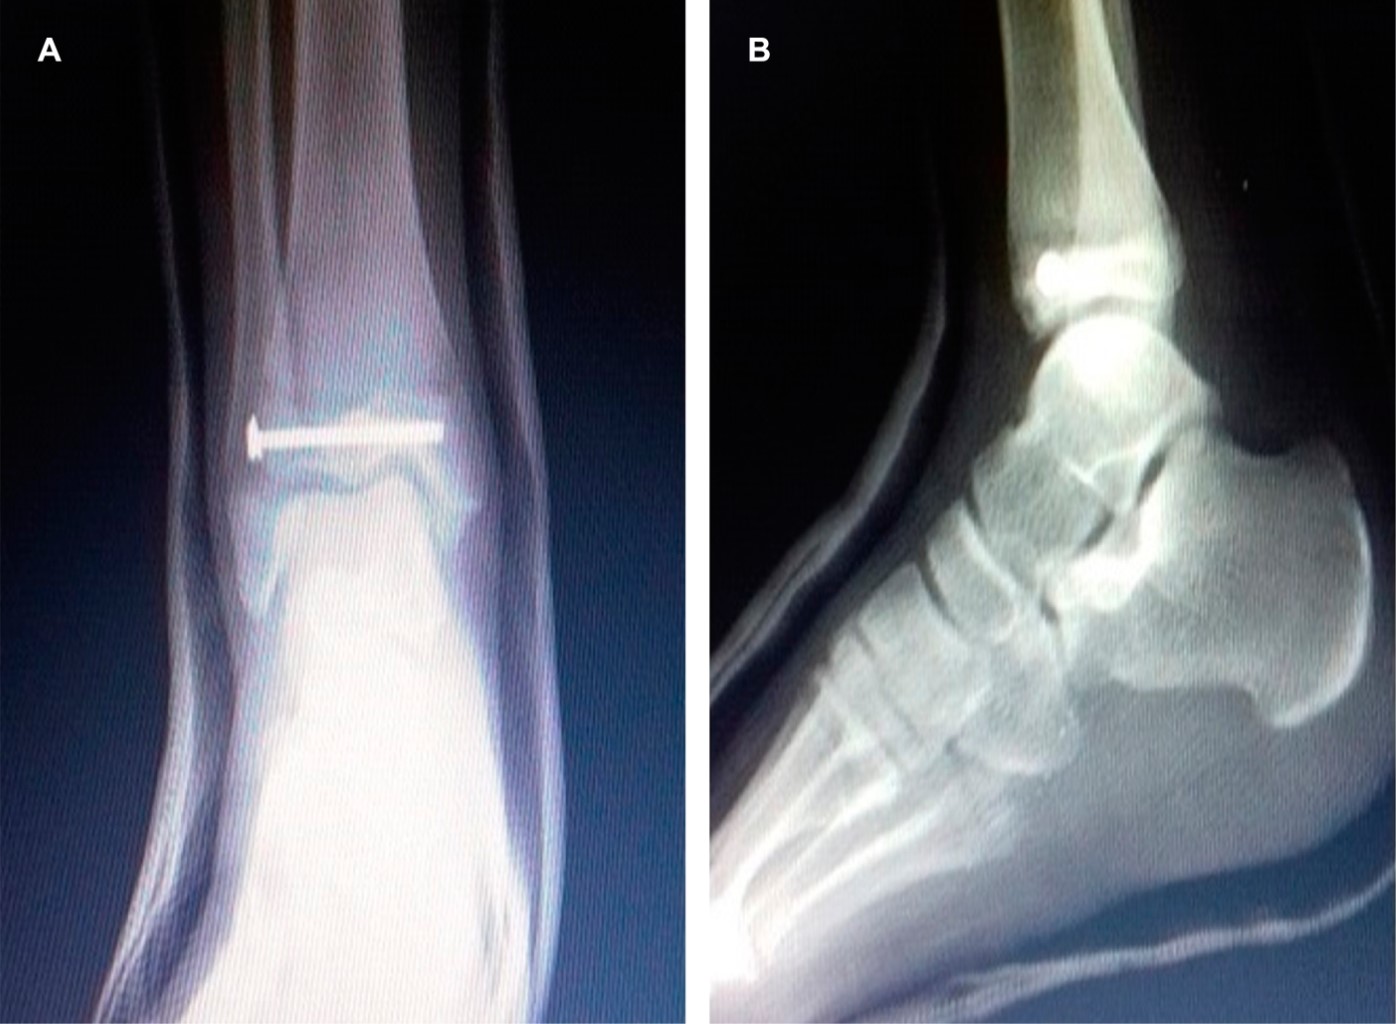

Se realizaron radiografías simples de tobillo (anteroposterior y lateral) y del pie (anteroposterior, lateral y oblicua), las cuales evidenciaron fractura de la porción distal de la tibia derecha, justo en la cara anterolateral, con trazo articular al tobillo y presentando escalón articular mayor de 2 mm. Se clasifica lesión ósea como fractura Salter y Harris tipo III/fractura de Tillaux (Figura 1A y B).

Figura 1